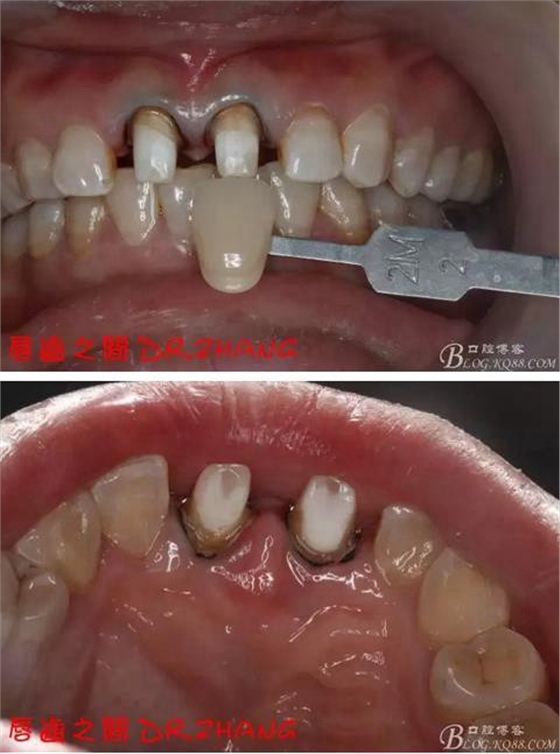

檢查:11 21金屬烤瓷冠 21根尖部牙齦紅腫 牙痛 叩(+++)冷刺激無反應(yīng) 11無不適癥狀 全口牙周情況良好

復(fù)診:腫脹明顯消失 患者自訴感覺良好 溝通后決定拆除11 21兩顆烤瓷冠后重新修復(fù) 去冠器直接去冠 去除11根管內(nèi)的充填物 15#K銼疏通根管 11 21根長均為16MM平斷面 薩尼S3系統(tǒng)機擴至2S 期間不斷用氯己定和鹽水交替沖洗 吸潮紙尖干燥根管后06 25#試尖

牙體預(yù)備后 硅橡膠取模 臨時牙恢復(fù)形態(tài)